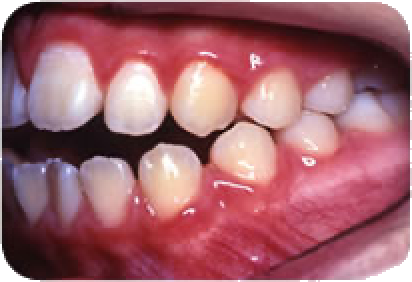

上と下の前歯があたらない(開咬)

奥歯を噛み合わせても、上下の前歯が開いていて、前歯で物を噛みきれない状態です。

舌で上下の前歯を押す癖があるとこのようになる可能性があります。 よくお子様の口元を観察して下さい。

このままの状態が長く続くと、ますます上下の前歯の距離が大きくなり、ものを噛みきれないのはもちろん、治療にも時間を要することになります。